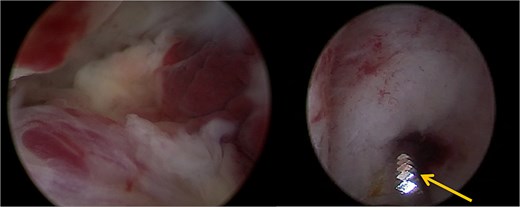

The patient opted for the latter. The procedure was performed in the operating room under spinal anesthesia due to the risk of hemorrhage. Using the TruClear System° (Medtronic) with saline irrigation, the remaining trophoblastic tissue was visualized and resected under direct hysteroscopic control. The soft tissue shaver was used with an oscillation speed of 1500 cycles per minute (Fig. 2). The procedure lasted 15 min, with no significant fluid absorption. The patient was discharged the same day without complications or significant bleeding. Histopathological analysis confirmed retained complete hydatidiform mole. hCG monitoring demonstrated normalization within 3 weeks following the procedure. Monthly hCG monitoring was then carried out for a period of 1 year while the patient was using effective contraception. Informed consent was obtained from the patient for the publication of this case.

A trophoblastic resection by hysteroscopic tissue removal system TruClear° was performed with the soft tissue shaver (arrow).